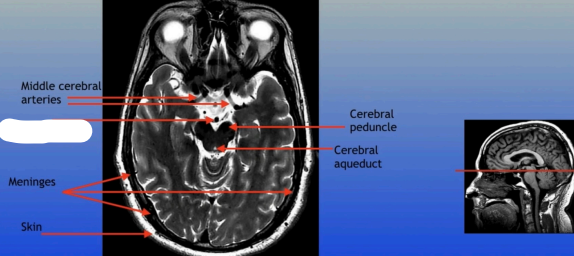

Middle Cerebral Arteries

Meninges

Skin

Cerebral Peduncle

Cerebral Aqueduct